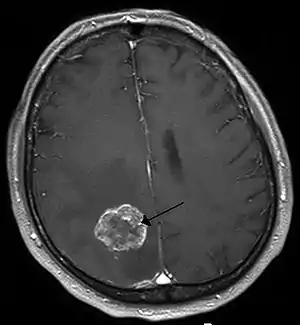

![]() Metastază cerebrală în emisfera cerebrală dreaptă, cauzată de cancerul pulmonar afișată prin intermediul imagisticii de rezonanță nucleară. | |